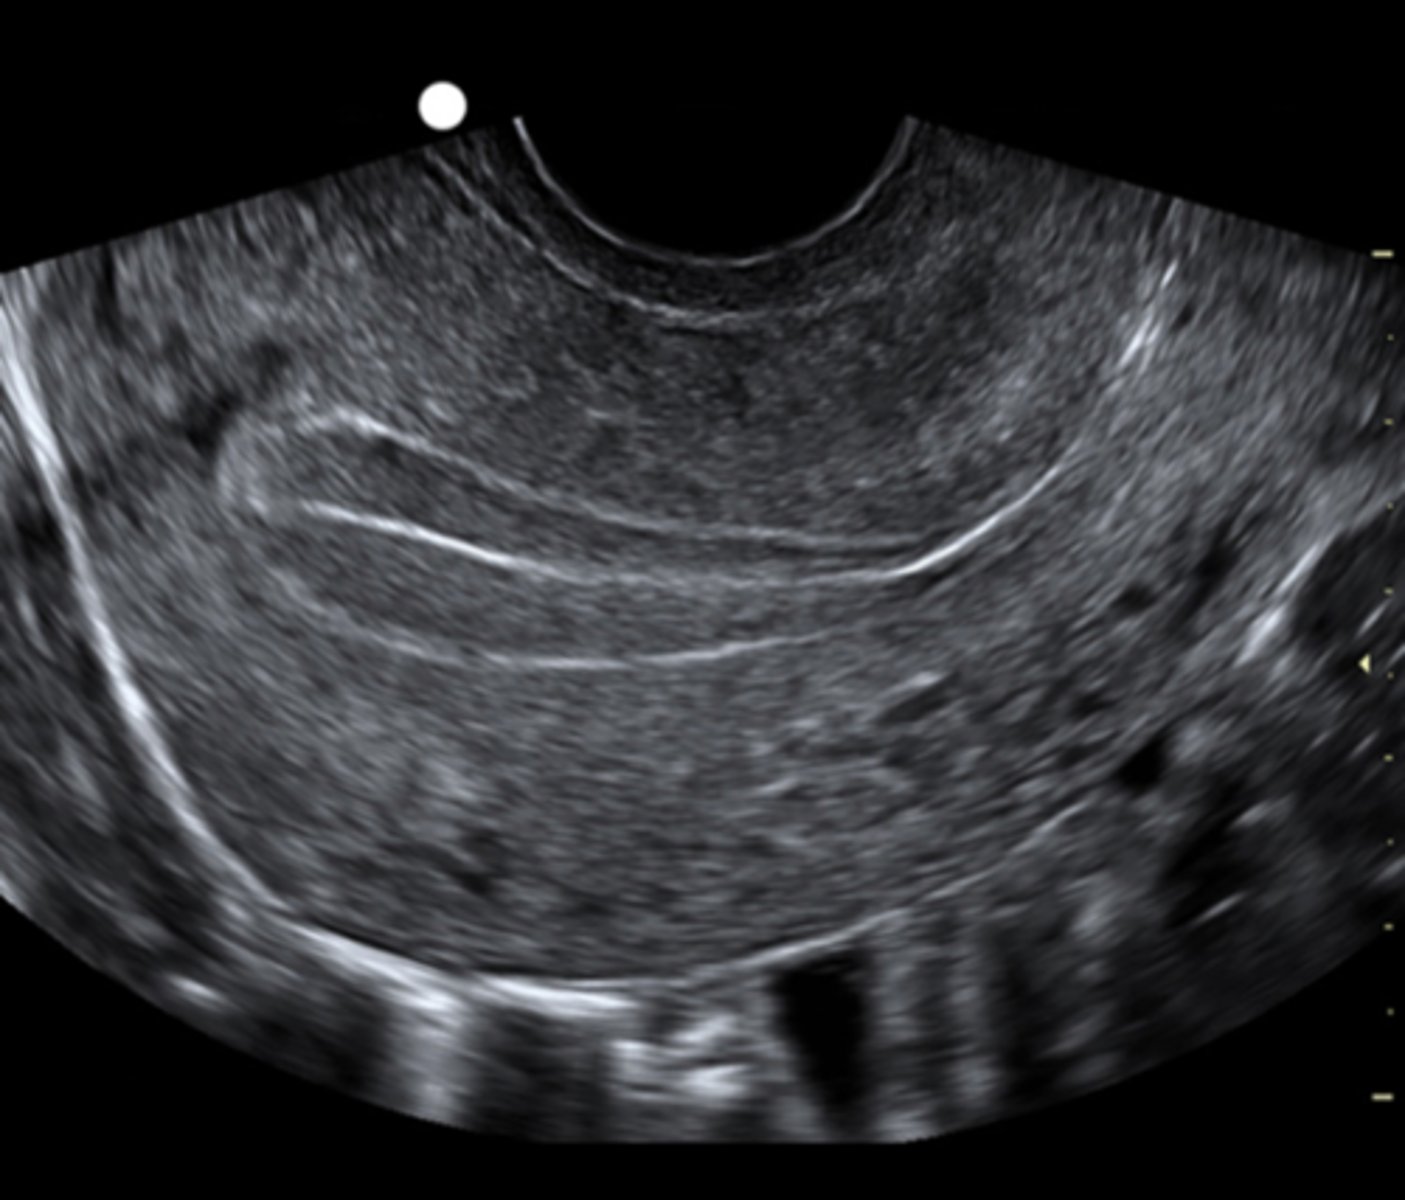

obtain baseline TV scan of ovaries to rule out cysts and assess for presence of dominant follicle

if cyst measuring greater than _____ detected, could represent persistent follicular activity that could interfere with response to ovarian stimulation medication

15mm